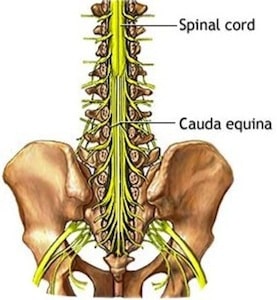

3. Cauda equina - fibrous strands extending from conus medullaris to coccyx ("horses tail”)--long ventral and dorsal roots.